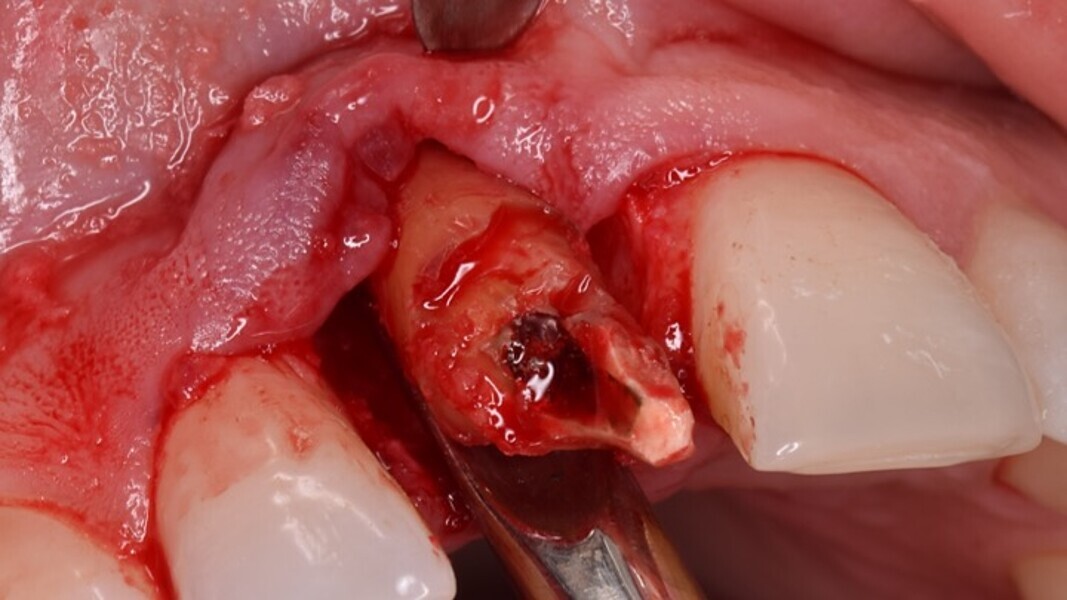

Figura 4. Exodoncia del diente.